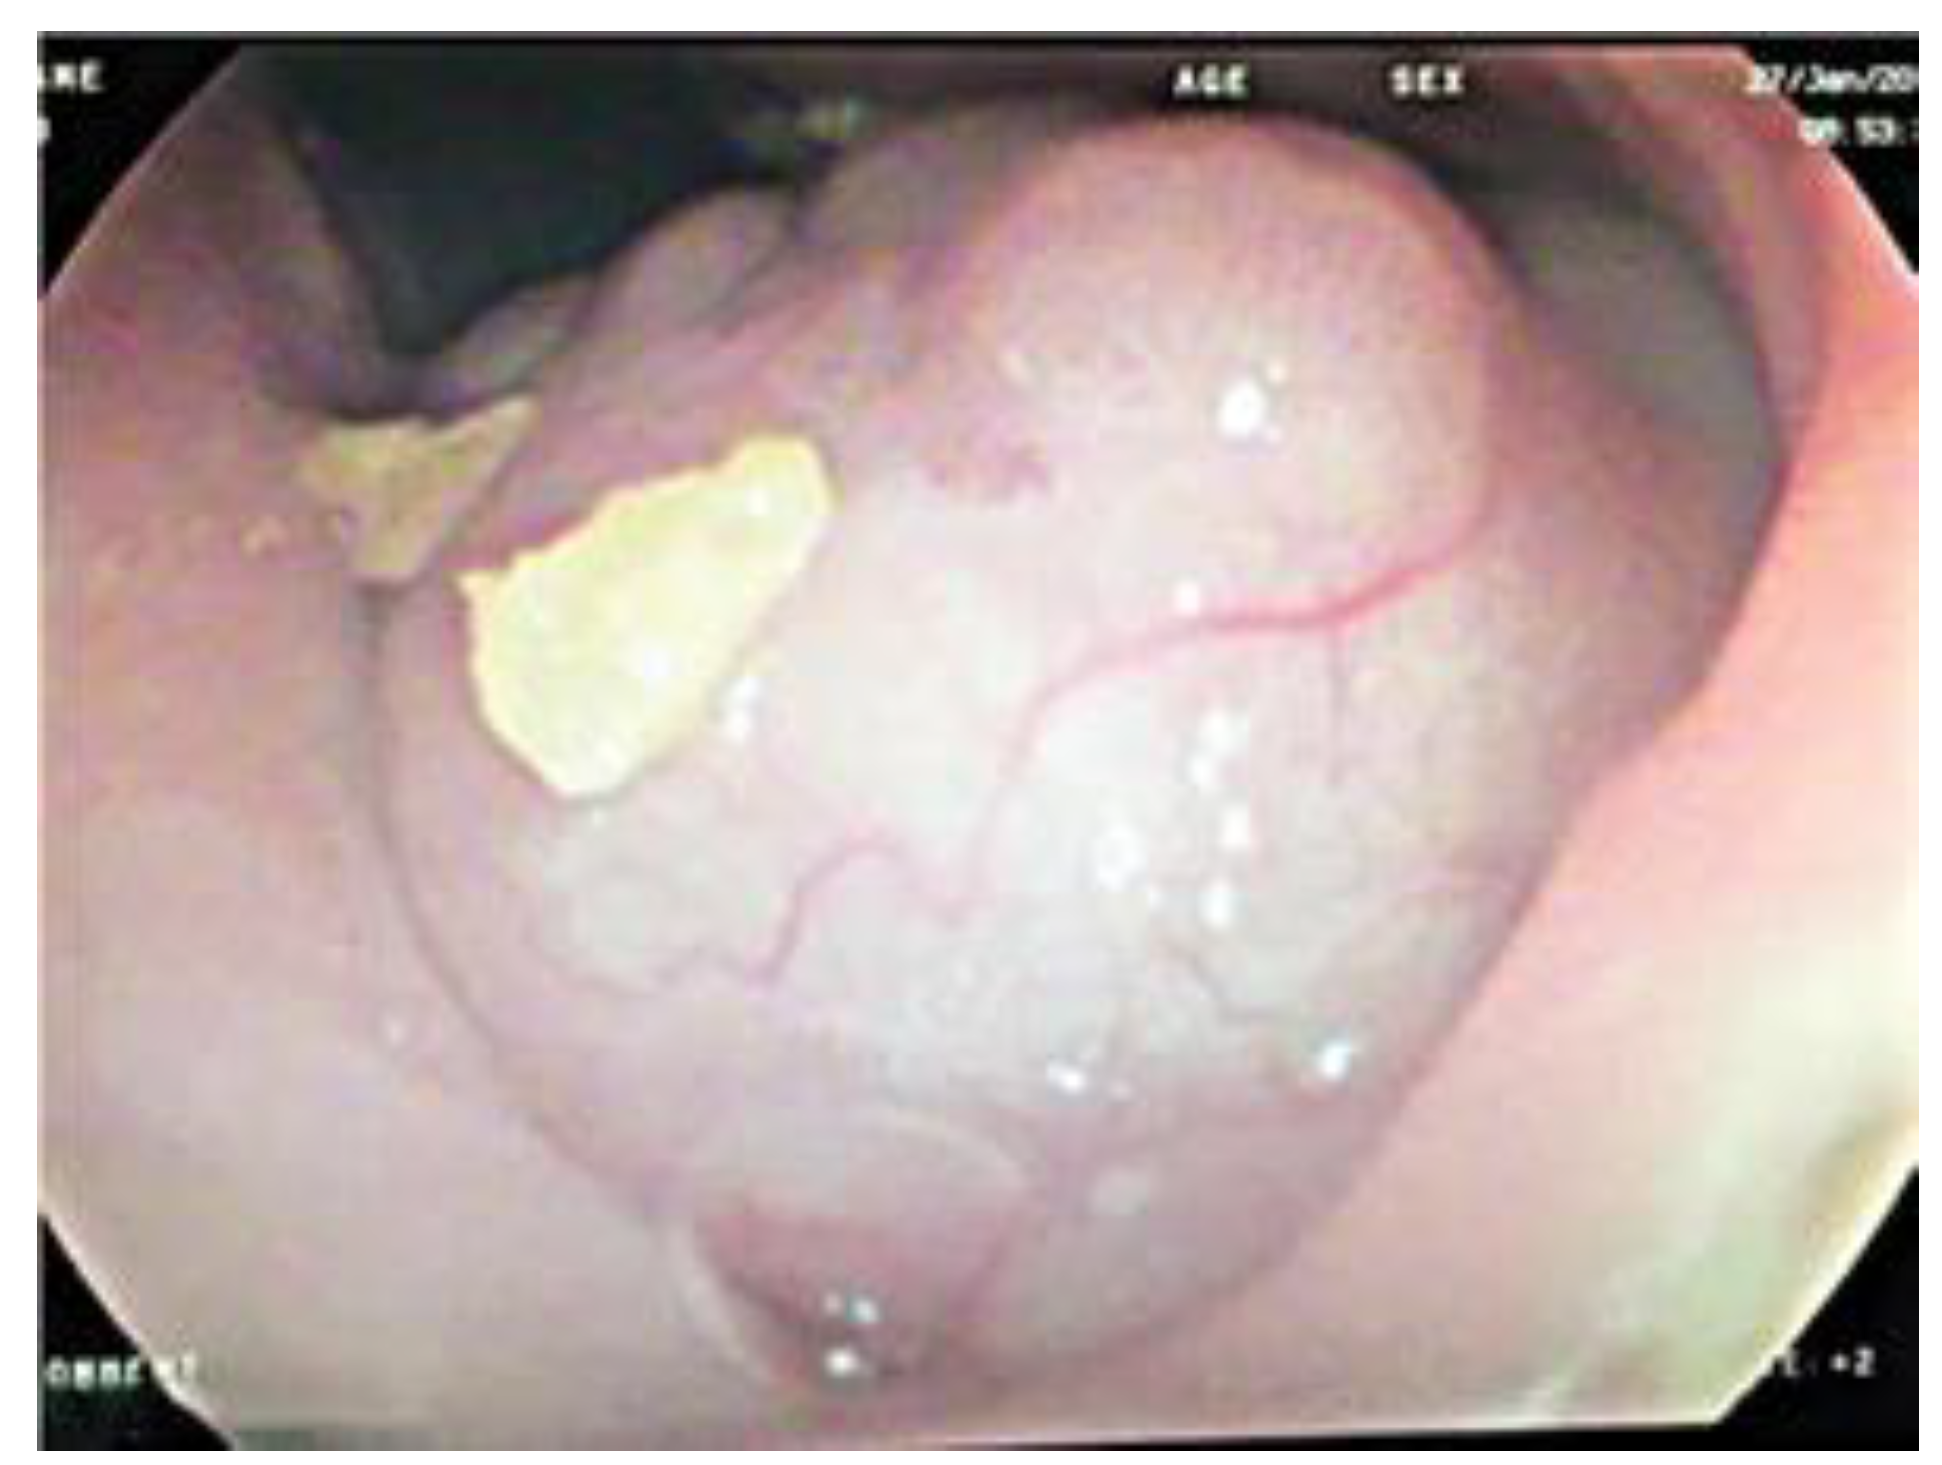

Case Report